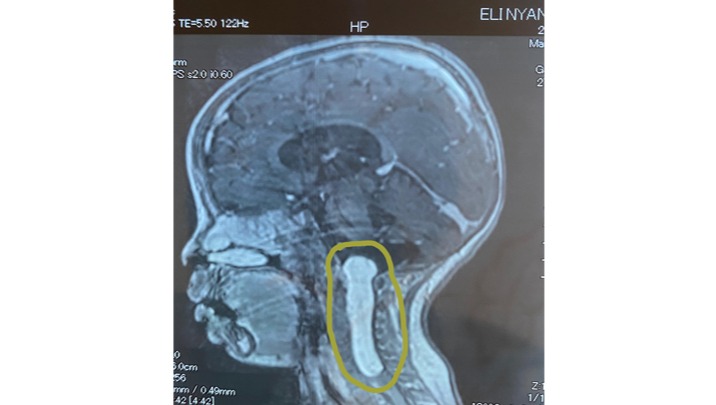

Our little sunshine, Eli, is just two years old, but his journey has already been filled with more challenges than most will ever face. From a young age, we could tell that his mobility (gross motor skills) was laboured. We went to multiple doctors, physicians, orthopedic surgeons, occupational therapists and physiotherapists here in Harare, Zimbabwe, trying to get an answer to what the underlying issue was, but we were never given a definitive answer. We were constantly told that developmental delays are 'normal' and that he would be fine, but as parents, you just know when something is off when it comes to your child. We were eventually sent for an MRI scan after a year of asking and that's when we unfortunately discovered a lipoma, a fatty tumor, growing on his spine and ultimately causing severe compression of the entire cervical spinal cord (C1 to T2).

This brave little boy has already undergone a laminectomy, a surgery to remove part of his spinal bone to access the tumor. Unfortunately, the surgeon discovered that the tumor was in fact, inside the dural sac and closer to the spinal cord than they'd initially anticipated and as such, could not be safely removed at that time. It's like a shadow trying to steal Eli's bright future. He needs another laminectomy to remove what can be safely removed of the tumor and give him a fighting chance at walking and exploring the world like any other child.